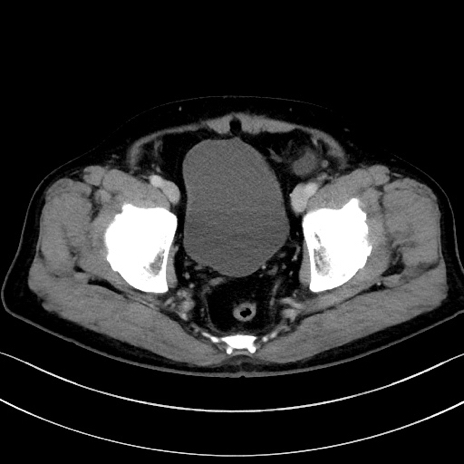

症例15(横断像)

【症例】70歳代男性

【主訴】腹痛

【現病歴】今朝から腹痛あり。全体的に痛い。特に左上の方。排ガスが今日はない。冷や汗が出る。

【既往歴】直腸癌術後

【身体所見】左側腹部〜上腹部に圧痛あり。腹膜刺激症状明らかなではない。軽度反跳痛。左下腹部に術後瘢痕あり。

【データ】WBC 7700、CRP 0.02